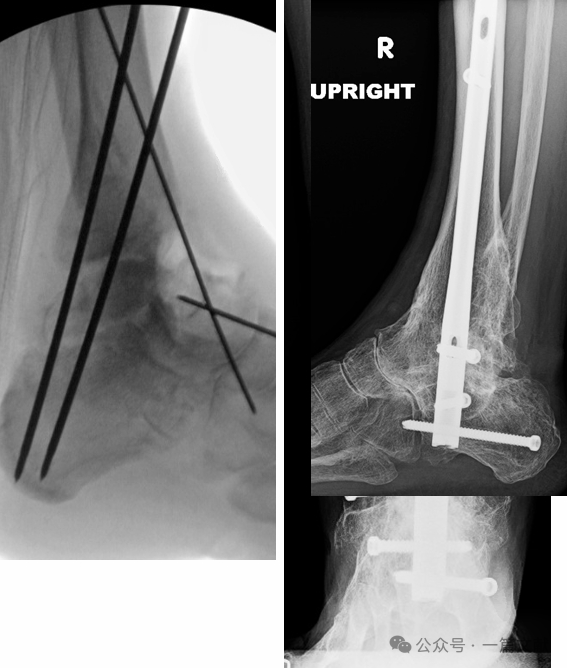

11.4 二次手术行逆行胫距跟关节(TTC)髓内钉固定的关节融合术。如下图: